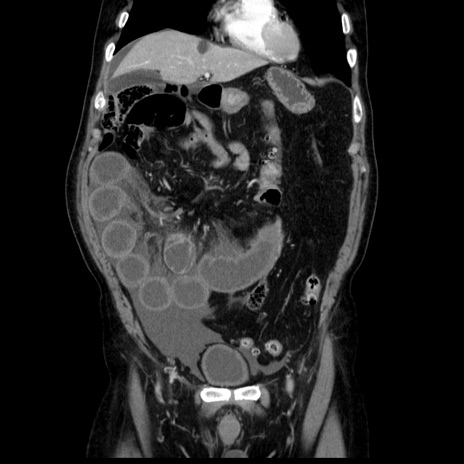

症例30(冠状断像)

【症例】80歳代男性

【主訴】臍周囲痛

【現病歴】約6時間前から臍下部痛が出現。次第に腹部膨隆・背部痛も生じてきたため来院。背部痛の場所は変化しない。

【既往歴】腎盂腎炎

【身体所見】意識清明、BT 36.3℃、BP  131/87mmHg、P 87bpm、SpO2 100%(RA)、臍周囲自発痛・圧痛あり、反跳痛なし、自発痛部位に一致して板状硬あり、腹部膨隆、腸雑音減弱、CVA tenderness両側陰性。

【データ】WBC 19600、CRP 0.33